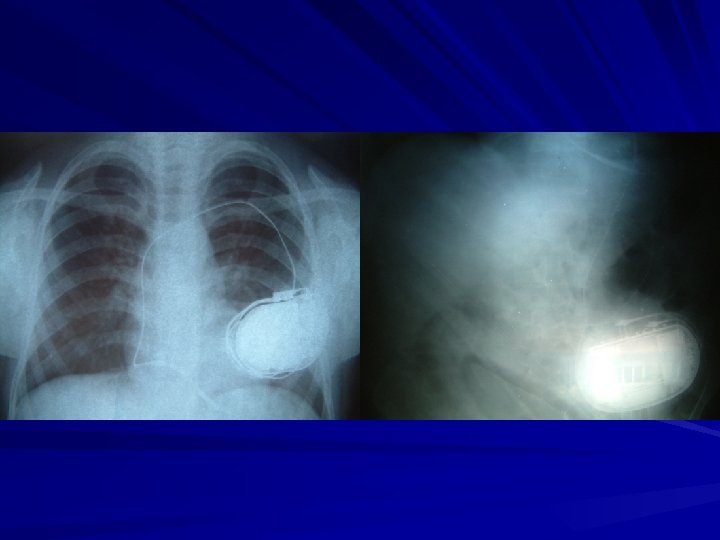

İmplante Edilebilen Kardiyoverter Defibrilatörler (İKD) Primer ve sekonder koruma amaçlı olarak kullanılabilirler. İKD kardiyak ritm monitörizasyonu yaparak aritmileri tanıyan ve çeşitli mekanizmalarla durduran cihazlardır. Son yıllarda kullanımları yaygınlaşmaktadır. Cihazla ilgili ilk çalışmalar 1960 yılında başlamış, insanda ilk implantasyon 1980 yılında yapılmıştır.